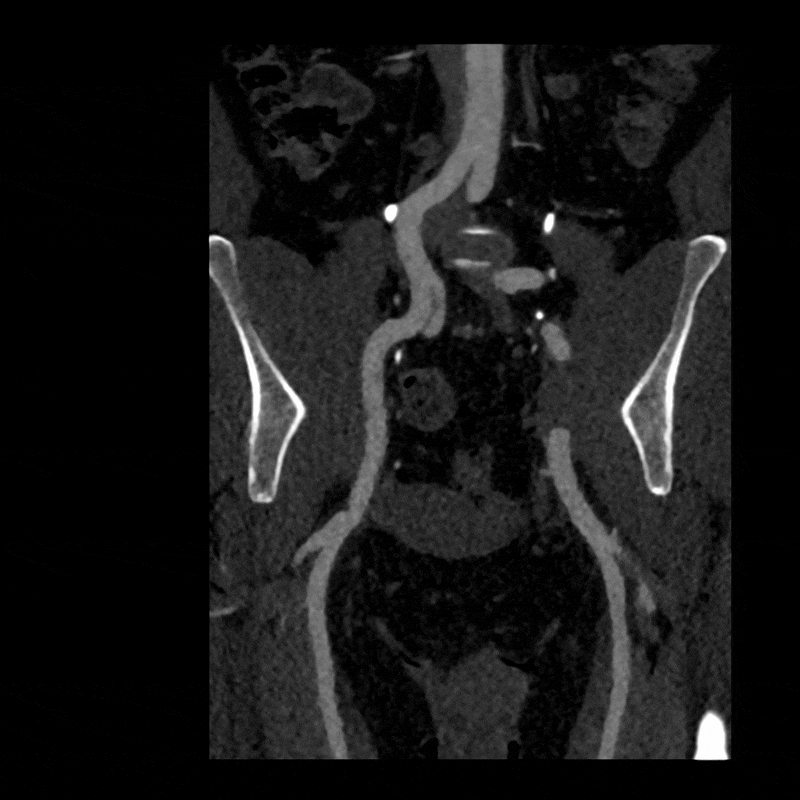

Figure B: Axial CT of the pelvis in a relaxed position.

Figure C: Axial CT in a stressed position.

To better visualize the iliac anatomy, CPR loops were created to trace the artery along its course in both relaxed and stressed positions, allowing direct comparison of lumen size and curvature. VR views were generated with and without pelvic and femoral bone to show surrounding anatomical relationships. These complementary views help clarify how limb motion influences vessel shape and highlight narrowing that may be subtle or difficult to appreciate on axial slices alone. (Learn more about CPRs here, and VRs here).

When the patient moved into the stressed position, the right external iliac artery showed two areas of luminal narrowing (a temporary decrease in the size of the vessel’s opening). One narrowing was more proximal (closer to the vessel’s origin near the pelvis) at about ten to twenty percent, and the second was more distal (farther along the vessel toward the leg) at about thirty to forty percent. Both returned to a widely patent appearance (fully open) when the leg moved back to a relaxed position.

The left external iliac artery remained patent across positions, and the common iliac arteries were tortuous (naturally curving) without any fixed stenosis. This pattern aligns with external iliac endofibrosis, where motion causes the artery to change shape rather than a fixed obstruction, highlighting why positional imaging can reveal abnormalities that may not appear on routine resting studies.